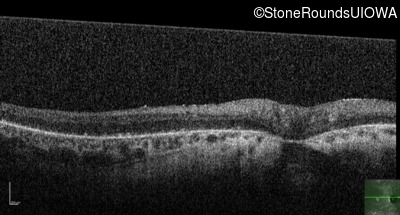

Optical Coherence Tomography - Left - 5/300

Exemplar / OCT Stack

OCT Stack